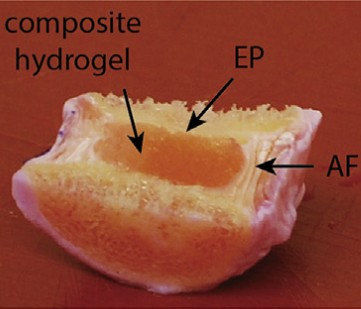

Karami P., Wyss C.S., Khoushabi A., Schmocker A., Broome M., Moser C., Bourban P., and Pioletti D.P., Composite Double-Network Hydrogels To Improve Adhesion on Biological Surfaces, ACS Appl. Mater. Interfaces, DOI: 10.1021/acsami.8b10735, 2018. |

Schmocker A., Khoushabi A., Frauchiger A. D., Gantenbein B., Schizas C., Moser C., Bourban P., Pioletti D., A photopolymerized composite hydrogel and surgical implanting tool for a nucleus pulposus replacement, Biomaterials, 88, 110-119, 2016. |